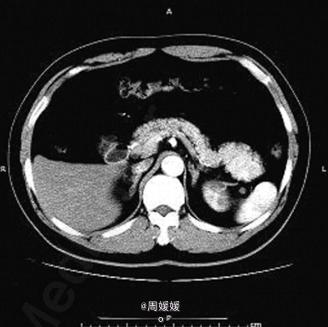

查体未见明显异常. 实验室检查:实验室检查 :肿瘤标志物甲胎蛋白 6.57ng/mL ,癌胚抗原3.64ng/mL ,糖类抗原1259U/mL ,糖链抗原19-9 12.30U/mL ,鳞状细胞癌相关抗原0.8ng/mL 。 B超提示:胰尾部可见一大小3.5cm*2.8cm 低回声区 ,边界尚清 ,内部回声不均。胰管不扩张。 增强CT提示:胰腺尾部可见一肿块影 ,大小约4.4cm*3.4cm*2.4 cm,动脉期、静脉期明显强化

诊断:胰腺尾部肿物 处理:腹腔镜下行镜下胰体尾切除术。

术后病理:送检组织镜下见为基本正常的胰腺组织 ,部分包裹脾脏组织 ,脾小体结构清楚 。符合(胰体尾)副脾。 本例分析误诊原因主要 :1.副脾发生在胰腺尾部,与胰腺关系紧密,CT 横断面不分辨其来源,造成误诊;2.胰腺异位副脾,临床非常少见,部分影像科医师主观上对副脾的认识不足,尤其不清楚副脾 CT 影像学特点,看见胰腺尾部富血供肿瘤,首先考虑胰腺神经内分泌肿瘤、囊腺瘤(癌),实性假乳头状瘤,而造成临床误诊。